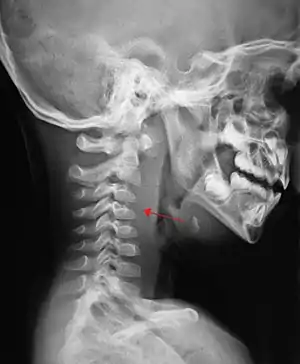

If more than half of the size of the C2 vertebra, it may indicate retropharyngeal abscess.[2]